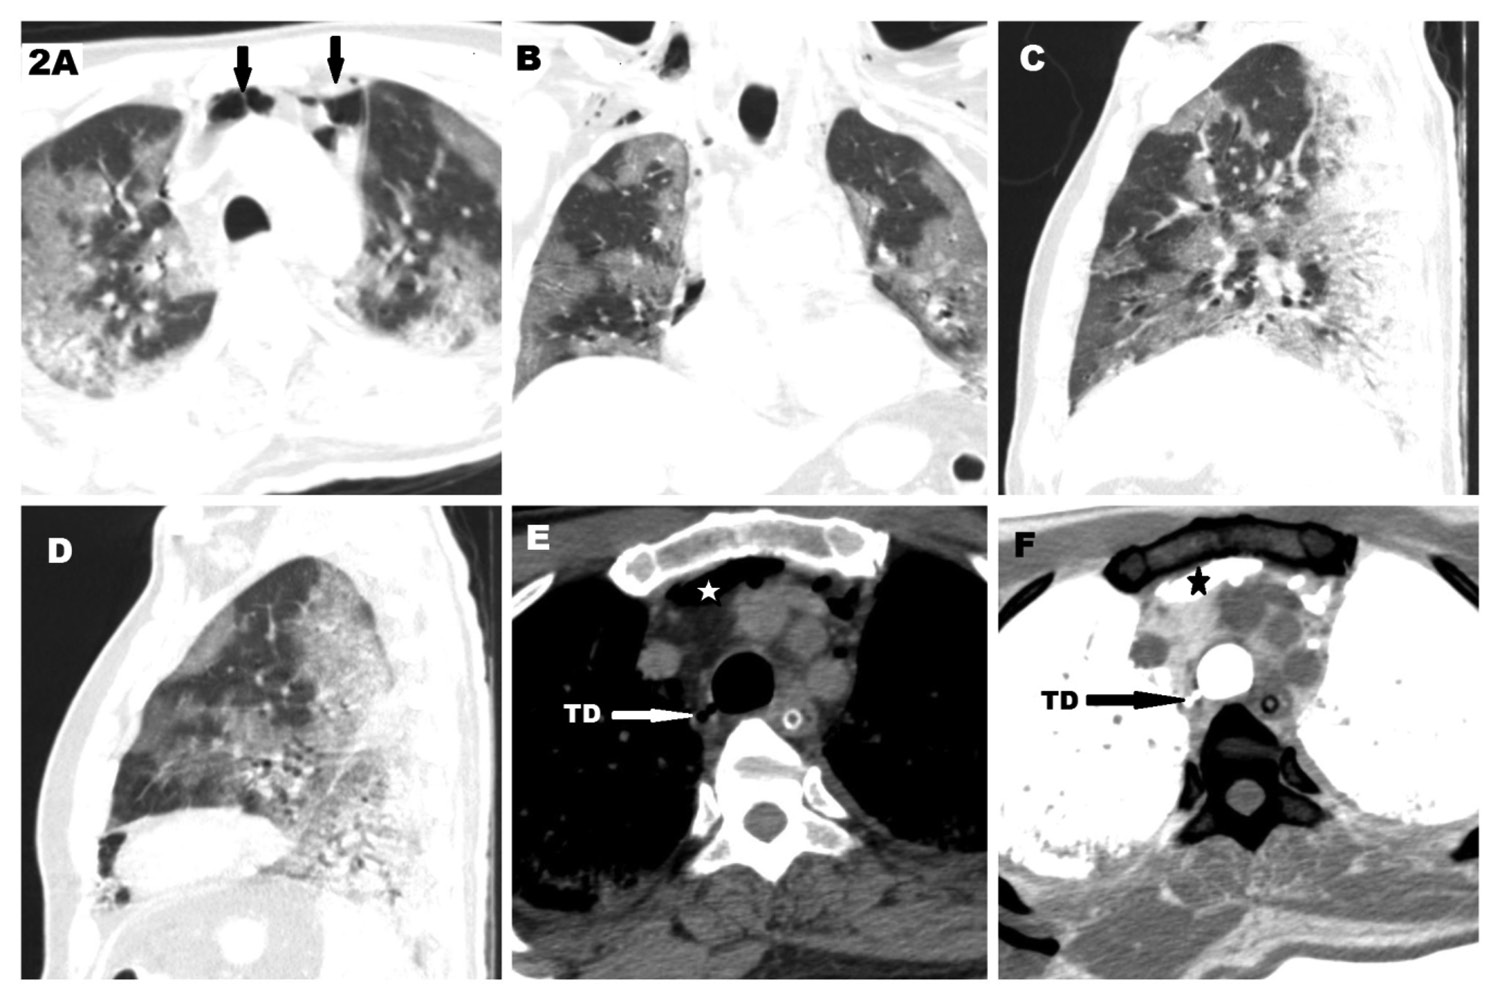

54-year-old man presenting with cough, breathlessness and fever for 5 days. He was RT-PCR positive for SARS-CoV-2. He had severe clinical pneumonia and CT severity score of 21/25. He required non-invasive ventilation to maintain oxygen saturation above 94%, with ventilatory settings of pressure support of 8 cm H2O and a positive end expiratory pressure (PEEP) of 5 cm H2O. Total duration of NIV support was 11 days. CT thorax was obtained which revealed confluent peripheral ground glassing with a few areas of interlobular septal thickening in bilateral lungs, predominantly in the lower lobes (Fig. 2 A-D). The overall lung involvement was given a score of 21/25 (severe pneumonia). The CT also revealed pneumomediastinum in the retrosternal location of the anterior mediastinum and subcutaneous plane of neck (Fig. 2 E-F). A small focal outpouching was noted from the right posterolateral wall of trachea (Fig. 2 E). This was better appreciated after inverting the images in mediastinal window to allow better contrast between the mediastinal fat and air (Fig. 2 F).

Figure 2. CT scan of a 54-year-old male with severe Covid 19 pneumonia. A. axial CT scan in lung window showing multiple peripheral ground glassing with pneumomediastinum (arrows) . B–D. Coronal, Sagital of right lung and Sagittal of left lung respectively showing peripheral ground glassings typical of covid 19 pneumonia. E. Axial CT scan in mediastinal window showing tracheal diverticulum (TD) and pneumomediastinum (star). F. Inverted CT image of the same showing better depiction of the diverticulum (TD).